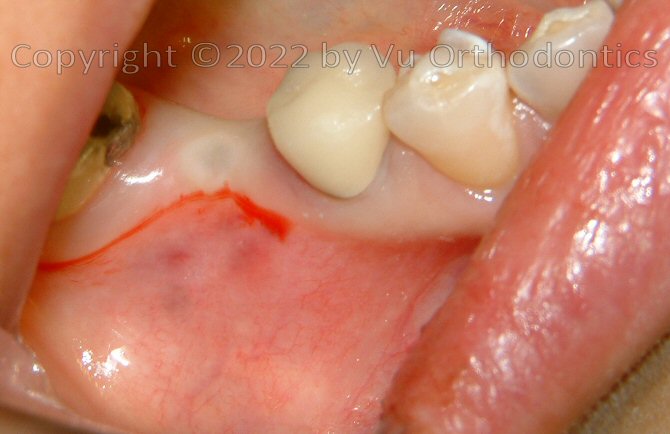

A Case that needs Free Gingival Graft (FGG)

For many patients, the posterior of the lower arch needs Free Gingival Graft (FGG) because of poor quality of keratinized mucosa. The case, infra, shows as an example.

Fig. 9. A broken 3-unit bridge (for the missing Tooth #30)

Fig. 10. Poor keratinized mucosa on the buccal side of the implant (with healing abutment)

Fig. 11. After the implant was buried (w/ a cap screw), ready for Free Gingival Graft (FGG), poor keratinized mucosa was apparent

Fig. 12. FGG was performed